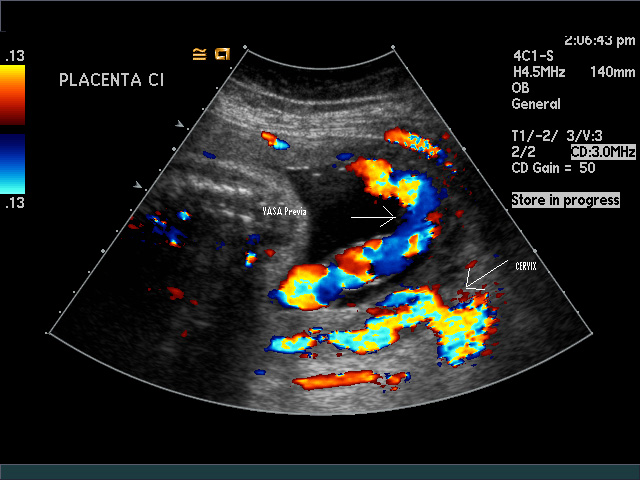

Vasa Previa

6. Vasa Previa — Valuable in diagnosis of a preventable problem. In all pregnancies it is now suggested that the cord insertion site in the placenta be recognized to prevent catastrophic bleeding with either labor or rupture of membranes. Color Doppler has also been used to identify a nuchal cord, cord entanglement, and fluid flow from the trachea, penis, and nasal passages.